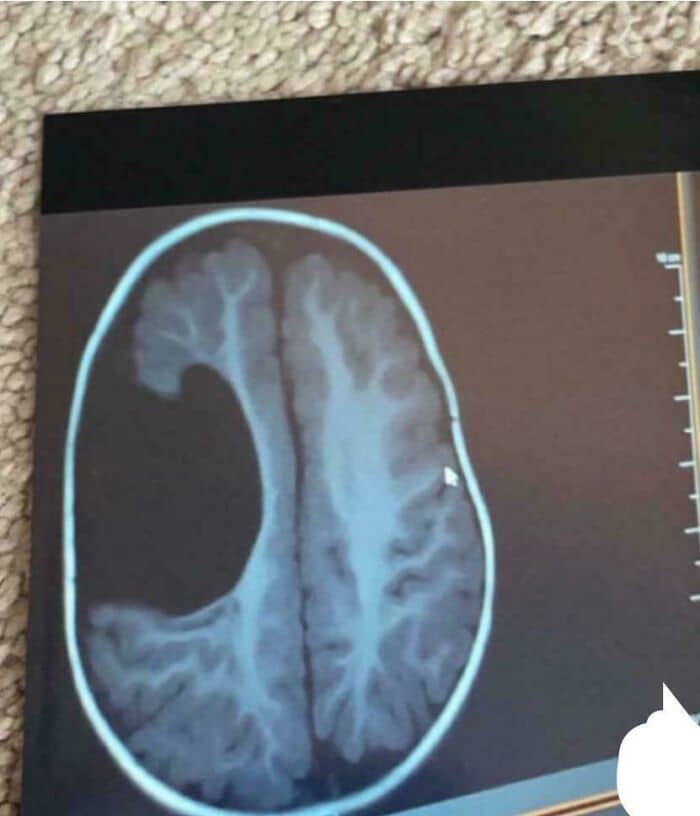

Well, there’s the whole thing about prions and their effect upon the brain. That’s spooky.

throwaway_78325:

As someone in healthcare, prion diseases. The more I learn about them the more I spiral. The random/genetic variants are the scariest but I live in an area where the majority of my friends husbands/boyfriends are hunters and bring home game meat and absolutely not, I politely decline any sort of meat they’re serving at their house. Keep that away from me.

noctenaut:

Prions.

Tiny little proteins inside your brain, they replicate themselves by folding and then forming out another prion.

Sometimes, they fold incorrectly, and then cause other prions to do the same – eventually, widespread misfolded proteins cause damage to the brain, and introduce prion diseases such as ‘Mad Cow Disease’ or ‘Fatal Insomnia’.

Prion diseases are unique, most pathogenic illnesses are caused by foreign bacteria, viruses, parasites and other tiny organisms – but prion diseases are caused by agents of your own body, not foreign.

As such, where antibiotics, antivirals and other means of therapy against a pathogen are largely effective – no such therapy exists against prion diseases. Cases are always fatal. A good example is fatal insomnia – as the prions damage the brain further and further, the ability to sleep becomes impossible and the victim must wait for the body to give up. Hell on earth.

Prions are also incredibly hard to destroy, being resistant to alcohol, radiation, boiling, freezing and other conventional sterilisation methods – sometimes slipping into the food chain via farm animals such as cows, (hence ‘Mad Cow Disease’).

The also differ from other pathogens in that a misfolded prion overrides other proteins’ normal behaviour and thus causes them to misfold too. No other pathogen has the same ability – weaponising your own tissue against you.

As such, the central nervous system and eye tissue of somebody with a prion diseases is extremely contagious and require specialist destruction.